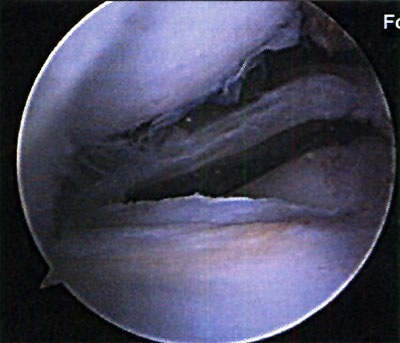

En cuanto a la localización de la lesión, 1 (2,4%) paciente presentó una localización anterior, 12 (29,3%) anterolateral, 23 (56,1%) posteromedial y 5 (12,2%) central. No se pudo explicar claramente esta distribución. (fotos 1 y 2) En cuanto a los casos presentados, los estudios radiográficos pusieron en evidencia la lesión en solo 36,6% de los pacientes, en 26 (63,4%) las radiografías fueron negativas (GI) mientras que de los casos positivos, 6 (14,6%) presentaron una lesión GIl, 6 (14,6 %) presentaron una lesión GIl y 3 pacientes (7,3%) una lesión G IV. (fotos 3 y 4)

Foto 1: lesión anterolateral

Foto 2: lesión posteromedial.